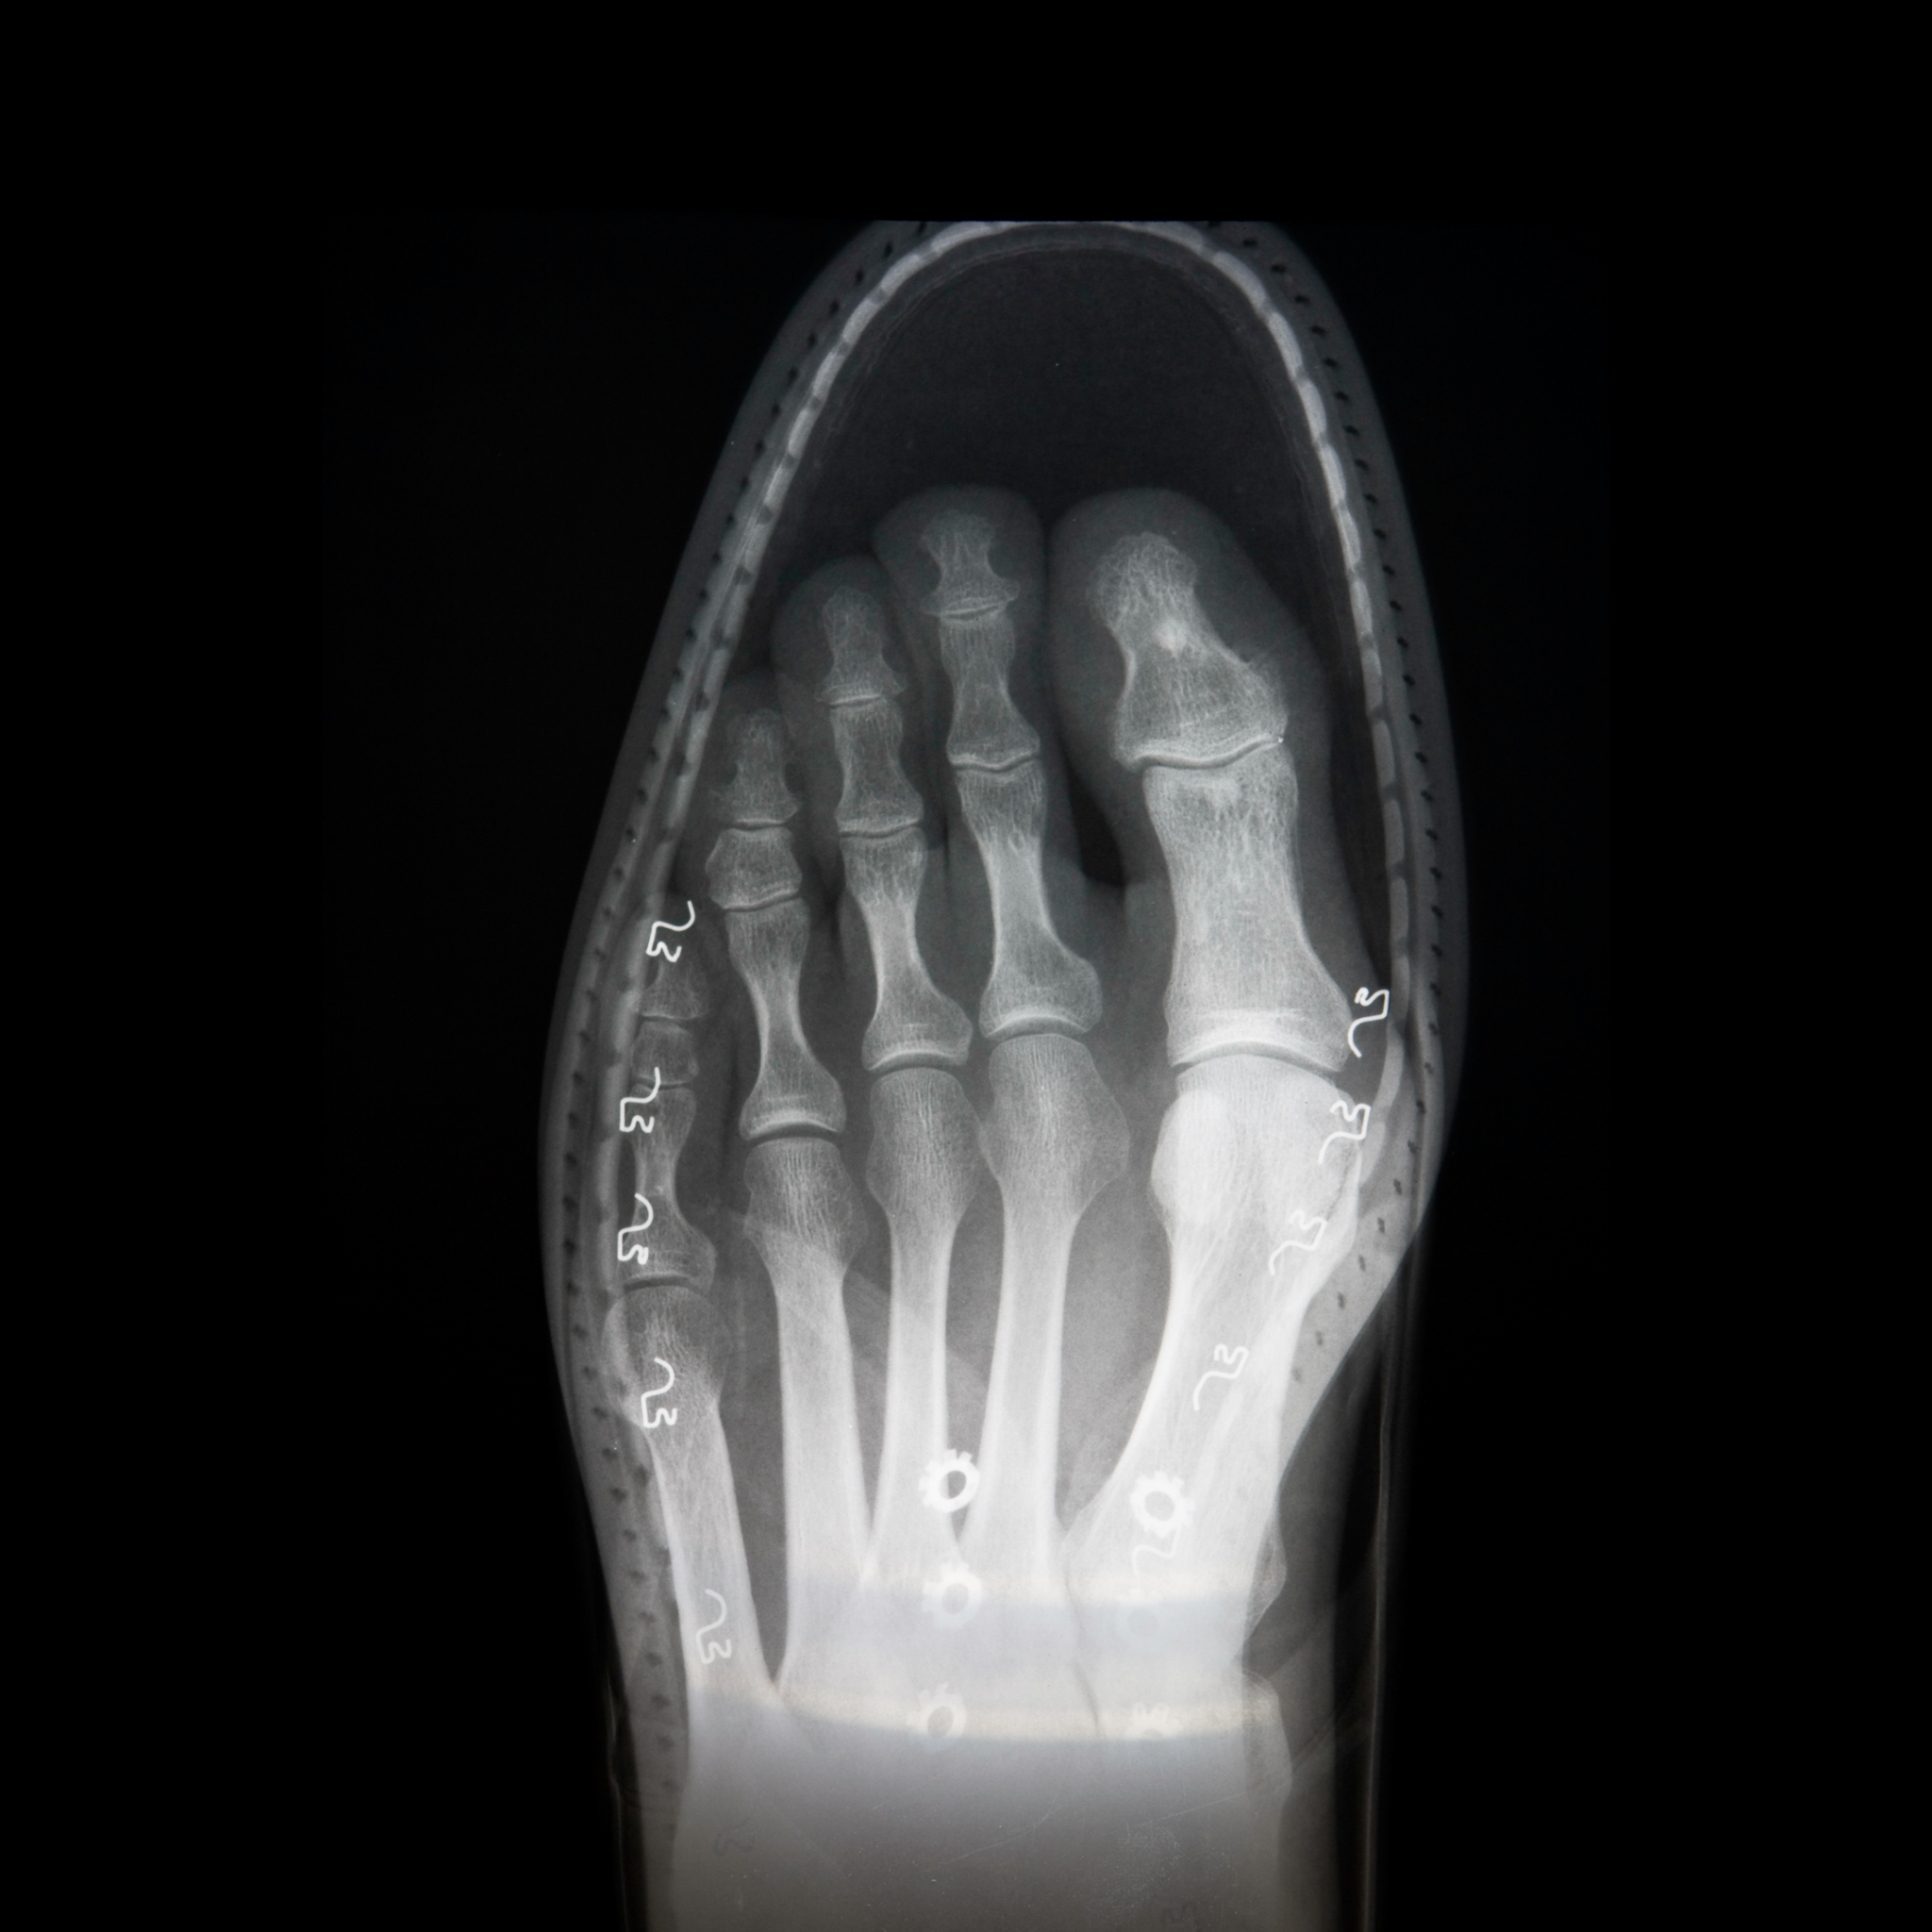

内反小趾とは?小指の痛みとどう関係するのか

内反小趾とは、

足の小指が親指側へ傾き、

小指の付け根の外側に出っ張りができる状態です。

英語では

Tailor’s bunion(テーラーズバニオン)

とも呼ばれます。

この状態になると、靴を履いたときに小指の付け根が外側から押されやすくなります。